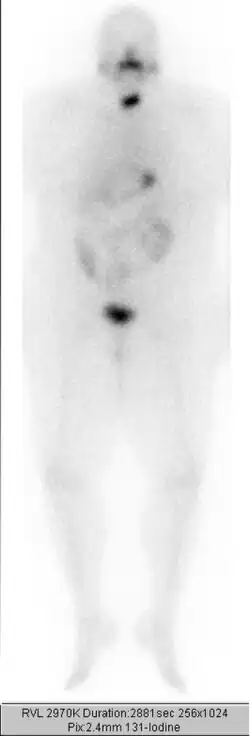

Einige Tage nach der Therapie wird ein Ganzkörperszintigramm angefertigt. Die Therapie wird in etwa dreimonatigen Abständen wiederholt, bis weder das Szintigramm, das Ultraschallbild der Halsregion, noch der Tumormarker Thyreoglobulin einen Hinweis auf nennenswertes verbliebenes Schilddrüsengewebe (gutartig oder bösartig) geben. Eine Gesamt-Aktivität über alle durchgeführten Radiojodbehandlungen von bis zu 74 GBq (2000 mCi) wird bei sonst gesunden Patienten meist problemlos vertragen. Bei höherliegenden Aktivitäten ist mit einem erhöhten Risiko für eine dauerhafte Schädigung des Knochenmarks als blutbildendes Organ zu rechnen.

Der Ablauf – mit Jodkarenz, Stimulation des TSH mit anschließender Bestimmung des Tumormarkers Thyreoglobulin und oraler Gabe des Jods sowie der Durchführung der Ganzkörperszintigrafie – entspricht dem Ablauf bei der ablativen Therapie. Unterschiedlich ist dagegen die Höhe der verabreichten Aktivität, üblich sind etwa 100 bis 400 MBq Jod-131 oder 40 bis 200 MBq Jod-123.